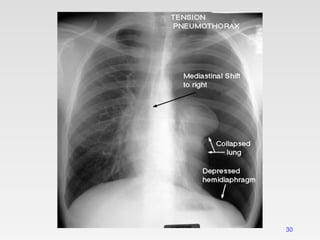

Tension pneumothorax

• Tension pneumothorax is classically characterized by

hypotension and hypoxia.

• It is life threatening condition.

• Rapidly progressive breathlessness and circulatory

collapse (tachycardia, hypotension & sweating).

• Jugular venous distention

• The pleural pressure is more than the atmospheric pressure.

Radiological manifestations of large pneumothorax

• Mediastinal shift,

• Flattening of the hemidiaphragm &

• Lung collapse.

It is more common with

• Positive pressure ventilation &

• Traumatic pneumothorax.

29

30